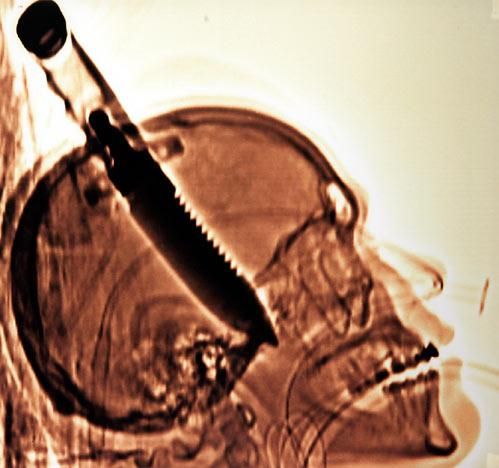

Radiografía de Michael Hill, de Jacksonville, Florida, con un cuchillo de ocho pulgadas enterrado en su cráneo.